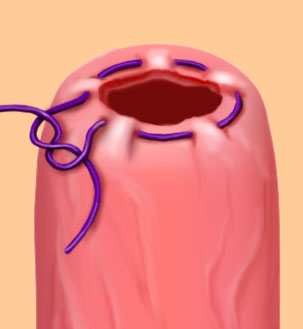

Purse String

A continuous stitch paralleling the edges of a circular wound. The wound edges are inverted when tied. Commonly used to close circular wounds, such as hernia or an appendiceal stump